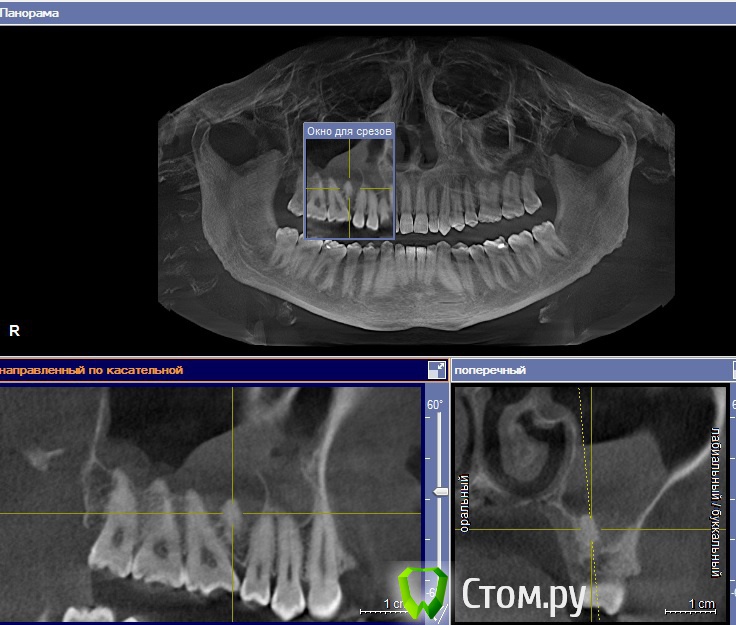

fmn Опубликовано 2 августа, 2014 Поделиться Опубликовано 2 августа, 2014 Здравствуйте! Пациент не мой, коллега попросила выложить этот случай на обсуждение, так как есть определённые затруднения с диагнозом. Из анамнеза - хронический гайморит. В качестве находки - симметричные новообразования между корней 5 и 6 зубов верхней челюсти. Смущает связь с изменениями в слизистой оболочки верхнечелюстного синуса. ЗЫ Сорри за нарезку - Галилеос самый мой нелюбимый просмотрщик. Если нужно, могу выложить архив с КТ.Какие мысли по диагнозу и тактике? Ссылка на комментарий

dr-krasnov Опубликовано 3 августа, 2014 Поделиться Опубликовано 3 августа, 2014 Антральный экзостоз, связи с изминениями слизистой нет. Буду признателен за ссылку на архив с кт в личку. Ссылка на комментарий

fmn Опубликовано 4 августа, 2014 Автор Поделиться Опубликовано 4 августа, 2014 (изменено) DS: Инородное тело (пломбировочный материал) верхнечелюстной пазухи слева. Хронический синусит слева или Инородное тело (корень2..зуба) верхнечелюстной пазухи слева. Хронический гайморит слева. Не соглашусь с диагнозом. У пломбировочного материала совсем другая рентгеноконтрастность. Я перебирал между сверхкомплектным, одонтомой и цементомой(пока не увидел отсутствие связи с корнями зубов). Но моя квалификация в рентгенологии оставляет желать лучшего, поэтому и спрашиваю. По идее это лечит гнойное ЧЛХ совместно с ЛОРом в стационаре с операцией под в/в наркозом и госпитализацией. Если хотите это делать в кресле то лучще с опытным ЧЛХашником и выездным наркозом, но это очень муторно в плане перевязок Человечество изобрело эндоскопическую хирургию. И зачем мне это делать самому, если есть специально обученные ЛОР-врачи для таких случаев. Изменено 4 августа, 2014 пользователем fmn 2 Ссылка на комментарий